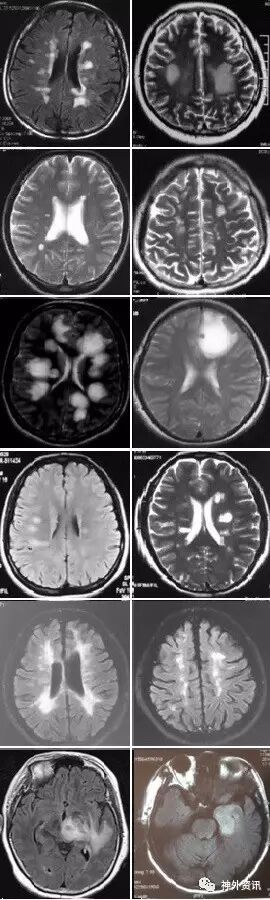

(重要申明:以下每个部分会配磁共振图片,因疾病和影像之间存在同病异象、同像异病,为避免误导,图片不标注疾病,其各自鉴赏,另其中的部分图片来源于网络,有疑问可与本人联系)

I--infection,感染

引起中枢神经系统病变的遗传性疾病可是种类繁多,主要指脑白质营养不良、脑小血管病等白质受累为主的病变。

如前者按发病机制可分为:溶酶体疾病(异染性脑白质营养不良、Fabry’s 病、Krabbe’s 病),过氧化物酶疾病(肾上腺脑白质营养不良(ALD)、肾上腺脊髓神经病(Adrenomyeloneuropathy))、线粒体疾病(MELAS、Leigh病)。按髓鞘病变病理过程种类分:异常髓鞘化:肾上腺脑白质营养不良、球形细胞脑白质营养不良、 染性脑白质营养不良;髓鞘化低下:佩梅氏病、Alexander病、白质消融性脑白质病;髓鞘囊性变性:Canavan病、空泡性脑白质病。

各种遗传性脑小血管病:如CADASIL、CARASIL、Fabry病及CAA、CAA相关性血管炎等等。

还有结节性硬化、各类NBIA(脑组织铁沉积神经变性病),脑肝肾综合征、线粒体脑病、LCC等。